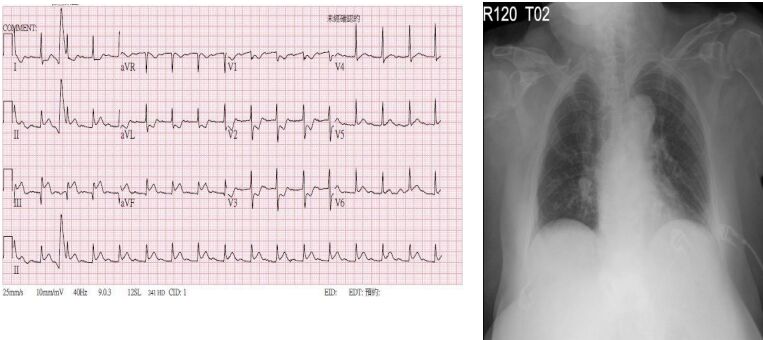

21. 黃先生68歲,有慢性阻塞性肺病(chronic obstructive pulmonary disease, COPD)的病史。因為發燒三天,合併呼吸急促與咳嗽有黃濃痰的狀況來到急診。黃先生自訴三個月前曾經因為慢性阻塞性肺病急性發 作(COPD exacerbation)住院一週,使用過類固醇與注射型抗生素。於急診時理學檢查發現呼吸急促,意識清楚。體溫 38.6°C, 心跳110 /minute, 血壓 136/80 mm Hg, 呼吸速率 26 /minute, 不使用氧氣的情況下SPO2: 91%,CXR如圖所示。WBC: 12,000 /mm³, platelet count: 159,000 per /mm³, BUN 26 mg /dl, creatinine 1.2 mg/dl。於急診的處置下列何者不適當?